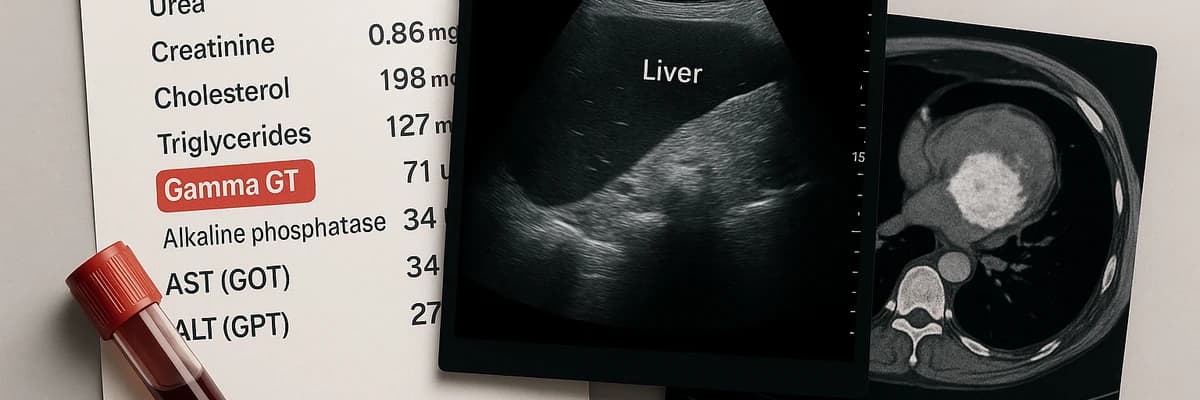

Les examens sanguins complémentaires indispensables

Quand un médecin détecte un Gamma GT élevé lors d’une analyse, la première étape est presque toujours de compléter le bilan sanguin. Pourquoi ? Parce que les Gamma GT, à eux seuls, ne suffisent pas à identifier la cause. Ils indiquent simplement une souffrance hépatique.

Transition : Les médecins prescrivent donc un panel d’analyses complémentaires. Celles-ci permettent d’orienter le diagnostic vers une atteinte hépatique, biliaire, ou métabolique. Voici les principaux examens.

1. Les transaminases (ALAT, ASAT)

En pratique, un taux élevé de Gamma GT + ALAT oriente vers une atteinte hépatique directe. En revanche, un Gamma GT élevé + ASAT peut révéler aussi bien une souffrance musculaire qu’hépatique. D’où l’importance de l’interprétation croisée.

Exemple concret : une hépatite virale entraîne presque toujours une hausse conjointe des ALAT et ASAT. En revanche, une consommation d’alcool chronique donne un profil particulier : ASAT > ALAT, avec Gamma GT élevé.

2. Les phosphatases alcalines

Les phosphatases alcalines (PAL) sont un autre marqueur clé. Elles augmentent surtout en cas de problème des voies biliaires (obstruction, calculs, cholestase).

Lorsque Gamma GT et PAL sont élevés simultanément, le médecin pense à une atteinte cholestatique. Cela oriente rapidement vers des examens d’imagerie (échographie, scanner).

Transition : Pour compléter ce tableau, un autre paramètre est scruté avec attention : la bilirubine.

3. La bilirubine

La bilirubine est un pigment issu de la dégradation des globules rouges. Sa valeur est très utile car elle reflète la capacité du foie à excréter la bile.

Une bilirubine élevée associée à un Gamma GT élevé évoque une obstruction biliaire ou une maladie hépatique avancée. Elle se manifeste parfois cliniquement par un ictère (jaunisse).

Point clé : Gamma GT élevé + bilirubine élevée = alerte, consultation rapide nécessaire.

5. Le bilan lipidique et glycémique

Pourquoi demander un bilan lipidique et glycémique ? Parce qu’un Gamma GT élevé peut être la conséquence d’un syndrome métabolique. Ce syndrome regroupe :

un excès de cholestérol et triglycérides,

un surpoids abdominal,

une résistance à l’insuline (diabète de type 2).

Dans ce contexte, le Gamma GT devient un marqueur indirect de surcharge graisseuse du foie (stéatose).

6. Le bilan sérologique hépatique

Enfin, le médecin peut demander des sérologies pour rechercher une hépatite virale. Les hépatites B et C sont particulièrement concernées car elles peuvent évoluer silencieusement pendant des années.

Le Gamma GT n’est pas spécifique d’une hépatite, mais il en est souvent un signal précoce associé aux ALAT/ASAT.